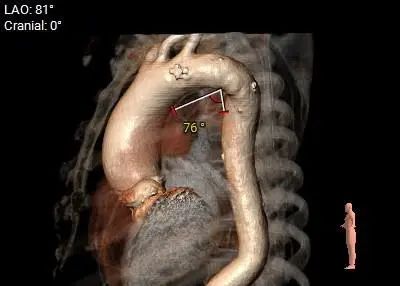

主动脉瓣环水平夹角71度,严重横位心,主动脉弓宽度、角度尚可,弓部存在散在钙化

虚拟瓣环与水平夹角

考虑右侧股动脉为主入路,左侧为辅助入路。严重橫位心,升主动脉扩张,弓部存在散在钙化,预估输送器过弓顺利,跨瓣难度增高。由于先天性二叶式主动脉瓣伴瓣叶重度钙化,瓣口限制明显,手术预装AV26备AV29瓣膜,根据20mm球囊预扩结果选择瓣膜型号,计划瓣膜释放定位深度接近瓣环。